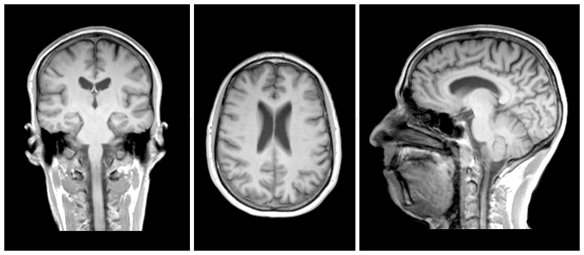

plan coronal

ou frontal

plan horizontal

plan sagittal